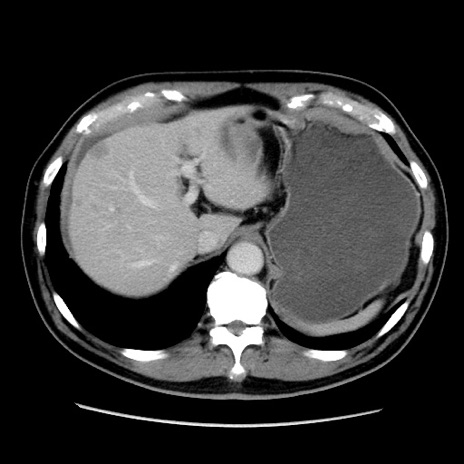

症例16(横断像)

【症例】 70歳代男性

【主訴】 腹痛、嘔吐

【現病歴】 約1ヶ月前より間欠的に腹痛と嘔吐あり、当院消化器内科を受診したところCTで多発する肝臓のLDAを指摘され、精査中であった。以降は消化器症状は安定していたが、2日前より嘔気と腹痛があり、同日より排便・排ガスが消失した。改善認めず、 本日、救急外来を受診した。

【既往歴】 大腸ポリープ切除後。

【身体所見】意識清明・会話良好、BT 36.3℃、BP 127/80mmHg、 P 80bpm、腹部:膨満あり、平坦・軟、上腹部正中および下腹部正中に圧痛あり、反跳痛なし、筋性防御なし。

【データ】WBC 7200、CRP 0.77